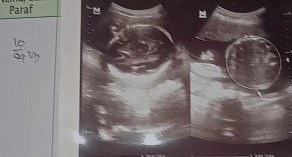

Bunda aku kan USG 2 Minggu yang lalu terus aku itu penasaran sama yang ada di foto ini itu apa ya

sebelah kiri perut, sebelah kanan kepala